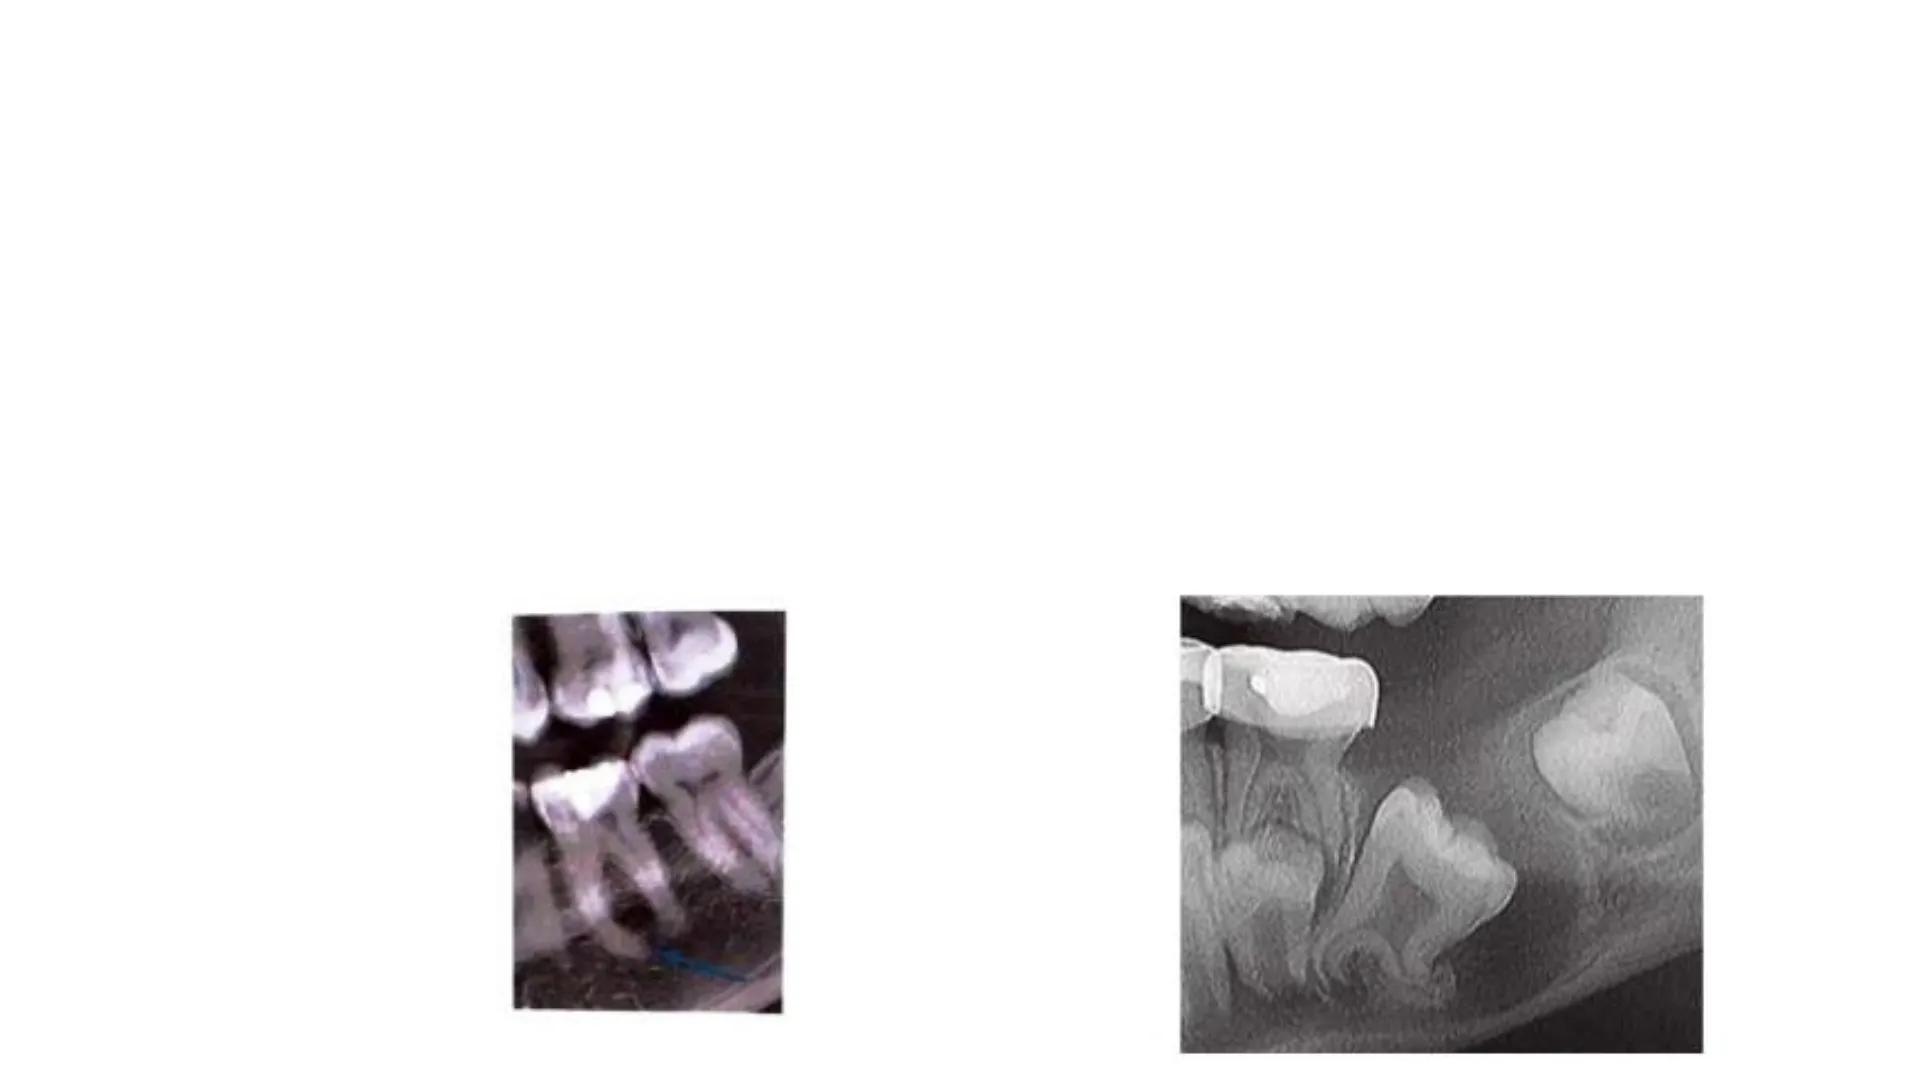

Las anomalías en la forma anatómica que pueden provocar alteraciones en la erupción dentaria son:

Entre las anomalías posicionales que pueden provocar alteraciones en la erupción dentaria, las más destacadas son las versiones o inclinaciones en cualquiera de sus formas:

Distoversión (inclinación a distal). Lateroversión (inclinación hacia vestibular o lingual). Mesioversión (inclinación a mesial). Figura 5. Caso 5 Fusión 7.1-7.2

Inversión (giro del diente de 180º). DTOS DE CASOS CLINICOS REALES TOMADAS CON CONSENTIMIENTO DE LOS PACIEN

Inclusión (diente incluido dentro del hueso). Impactación (diente parcialmente visible por erupción no completa)

Ectoptas (erupción en un lugar no habitual) Transposición (posición invertida de dos dientes adyacentes)